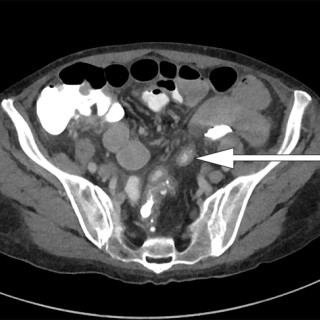

En yngre mann ble innlagt med venstresidige respirasjonsavhengige brystsmerter. Han hadde lett nedsatt allmenntilstand og feber. Det skulle bli et lengre sykehusopphold, der man diagnostiserte en uvanlig årsak til lungeaffeksjon. En tidligere frisk mann i slutten av tenårene ble via legevakt innlagt i sykehus etter ett døgn med venstresidige, respirasjonsavhengige smerter. Ved innkomst hadde han temperatur 37,6 °C, puls 117 slag/min, blodtrykk 104/57 mm Hg, respirasjonsfrekvens 24/min og perifer O2-metning på 94 % uten ekstra oksygentilførsel, og normale forhold ved klinisk undersøkelse...